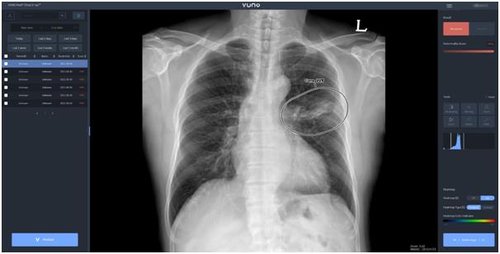

(서울=연합뉴스) 김잔디 기자 = 뷰노[338220]는 인공지능(AI) 기반 흉부 엑스레이 영상 판독 보조 솔루션 '뷰노메드 체스트 엑스레이'가 사우디아라비아 보건당국으로부터 의료기기 인증을 획득했다고 22일 밝혔다.

이 제품은 흉부 엑스레이 영상에서 결절, 경화, 간질성 음영, 흉수, 기흉 등 주요 이상소견을 탐지하는 AI 솔루션이다. 의료진에게 이상 소견과 위치를 제시해 결핵, 폐렴 등 주요 폐 질환 진단을 돕는다.